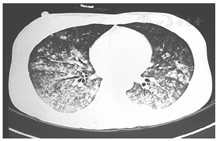

7月12日床旁胸部X线片(图3)示病灶好转吸收,完善风湿三项、免疫六项、自免十二项、结核抗体、抗中性粒细胞胞质抗体、磷脂综合征二项以及G试验,结果回报均阴性。至7月14日患者情况保持稳定,甲泼尼龙琥珀酸钠予逐渐减量,改为80 mg静脉滴注,每8 h 1次,并复查骨髓检查。7月15日床边胸片示病灶继续吸收,停无创呼吸机后复查血气仍提示Ⅰ型呼吸衰竭,深部痰培养出产超广谱β内酰胺酶的肺炎克雷伯菌(亚胺培南敏感),改亚胺培南西司他丁钠、伏立康唑维持,骨髓涂片报告当日回复:骨髓增生减低,G=41%,E=1.5%,G/E=27.67∶1。粒系增生减低,可见约7.5%原始、早幼粒细胞,破碎细胞易见,提示疾病未缓解,予亚砷酸10 mg静脉滴注,每日1次,继续诱导分化。7月18日情况稳定,甲泼尼龙琥珀酸钠继续减量,改为80 mg静脉滴注每日2次,其后每3~4天予减量1次,减至10 mg后维持至出院后。7月22日血常规:白细胞计数1.92 × 109/L,中性粒细胞计数1.56 × 109/L,血红蛋白83 g/L,血小板计数91 × 109/L,粒细胞缺乏恢复,情况稳定,停无创呼吸机。8月12日(亚砷酸治疗第29天)复查骨髓:骨髓涂片:骨髓增生活跃,粒系增生活跃,见个别早幼粒细胞,分叶略多于杆状核粒细胞。PML-RARα融合基因拷贝数<20,PML-RARα/ABL1<0.001。免疫残留:原始-前体细胞约占有核细胞的0.5%,CD34+细胞约占0.09%,未见免疫表型明显异常的细胞。评价疾病完全缓解。改甲泼尼龙10 mg每日1次口服维持治疗。8月11日复查胸部CT炎性反应基本吸收(图4),患者情况稳定于8月16日出院。8月22日复查胸部X线片(图5)心肺均未见病变,无呼吸系统后遗症,停甲泼尼龙。定期返院序贯诊疗,疾病均未复发,至今生存。